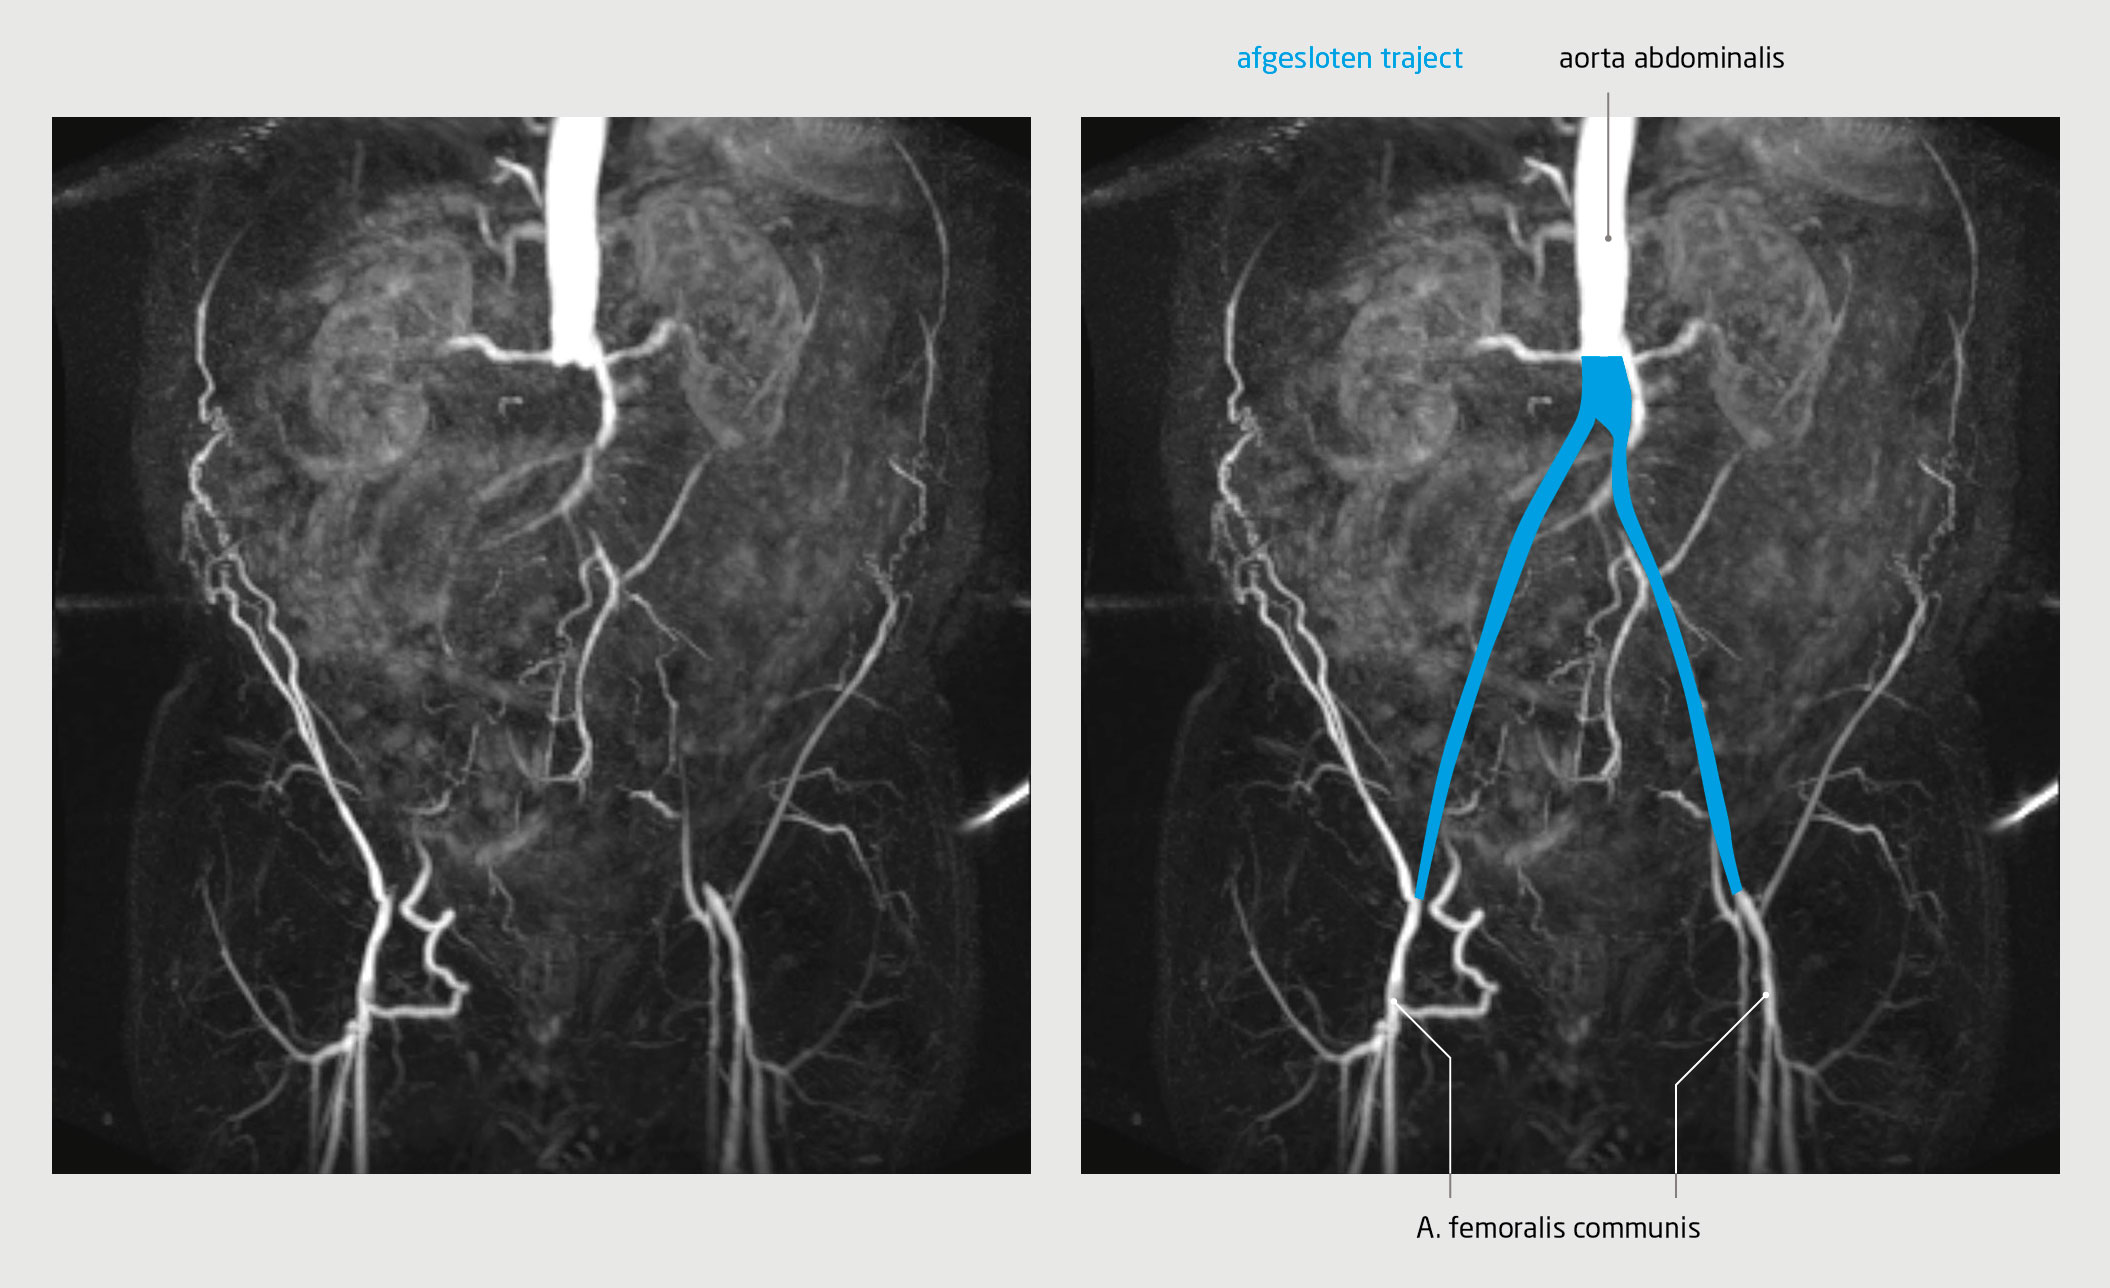

Sensibele en motorische uitvalsverschijnselen van de onderste extremiteiten kunnen het gevolg zijn van een centrale arteriële occlusie. In deze klinische les beschrijven wij het ziektebeloop van drie patiënten bij wie pas op een later moment gedacht werd aan een vasculaire oorzaak. Bij twee van de drie patiënten trad een vertraging op in het stellen van de diagnose en het begin van de behandeling. Deze klinische les benadrukt het belang van gedegen lichamelijk onderzoek bij patiënten met sensibele of motorische klachten van de onderste extremiteit, inclusief palpatie van perifere arteriële pulsaties.

Patiënt A, een 63-jarige man, heeft sinds 6 jaar geleidelijk toenemende sensorische en motorische klachten van de beide benen, pijn bij het lopen en erectieproblemen; deze klachten verergerden progressief na het plaatsen van een totale heupprothese, 5 jaar geleden. Hiervoor wordt hij gezien door een orthopedisch chirurg. De pijn en het dove gevoel van met name de lage rug…